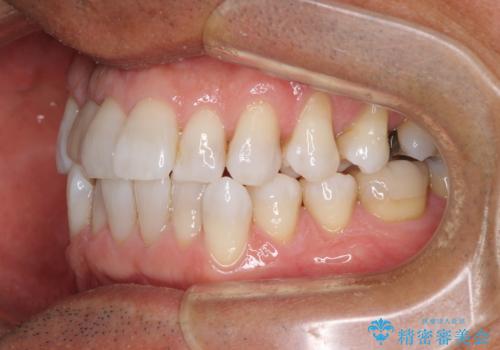

治療途中の前歯を治したい インビザライン矯正とオールセラミッククラウン

- 治療途中の前歯と上下前歯のデコボコ気にして来院された患者様です。

前歯のデコボコはインビザラインにより歯列を整え、その後に、前歯などをオーダーメイドタイプのオールセラミッククラウンにて補綴治療することとしました。

長時間のマウスピース装着に協力いただき、短期間で歯列をしっかりと改善することができました。

ホームホワイトニングを併用していただいたので、とても明るい口元に仕上がり、患者様には大変満足していただきました。